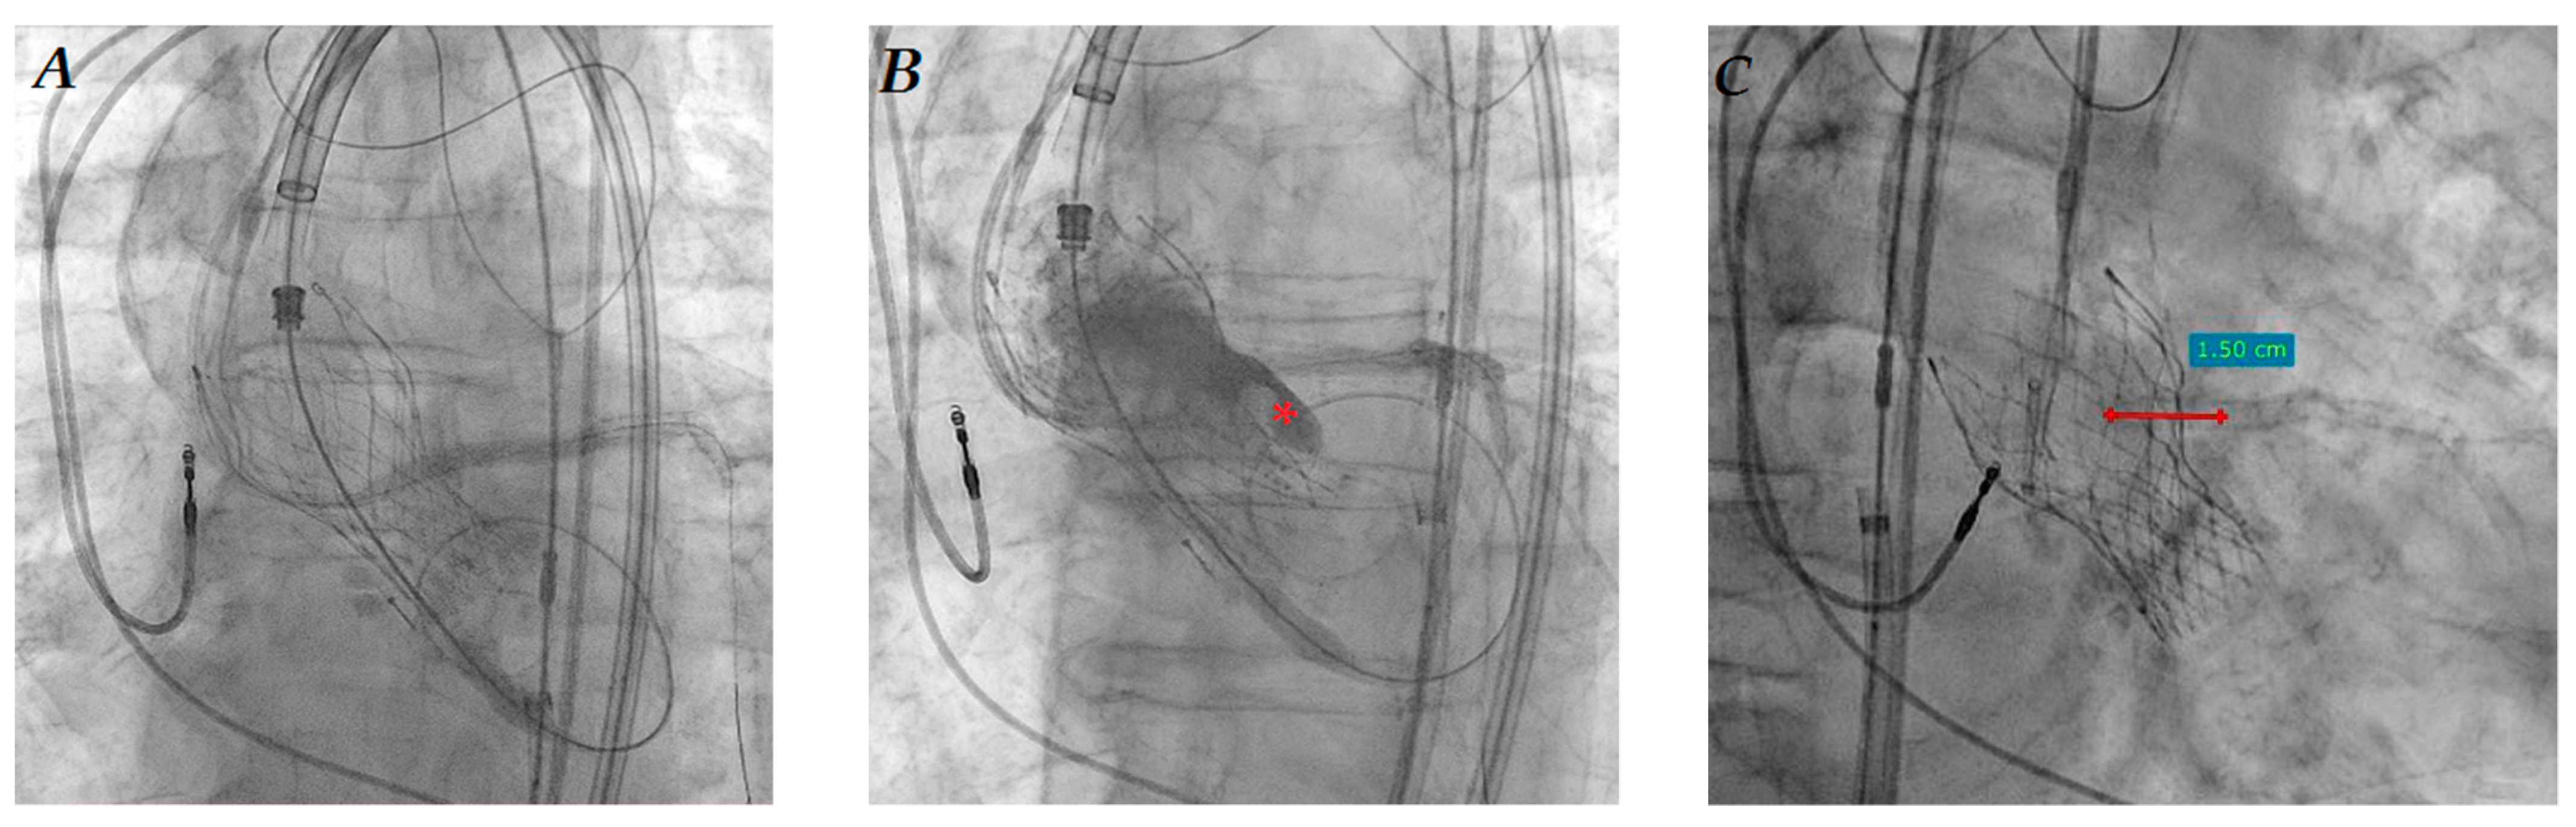

During valve inflation, the coronary guiding catheter was temporarily retrieved, while the new stent was kept in position with sufficient aortic protrusion, ready for immediate implantation (Figure 3A). After valve delivery, a subselective angiography showed reduced LMCA flow due to a displaced surgical bioprosthesis leaflet. The stent was then pulled back, expanded, and postdilated until 20 atmospheres through a 4.5 mm non-compliant balloon (Figure 3B). The “chimney stent” protrusion into the ascending aorta was about 13 mm (Figure 3C), which was close to the estimated implanted valve height of 14 mm. A contemporary “kissing” valve and stent postdilation was not necessary because of an optimal result. Guidewire “stent recrossing test” confirmed the optimal stent placement, just as a chimney parallel to the last implanted valve (Figure 3D), preserving a possible LMCA access for further coronary interventions.

Figure 3. “Chimney stent” (asterisk) positioning in LMCA and previously implanted LMCA edge aortic protrusion (arrow) immediately before valve implantation (A); “Chimney stent” protrusion into aorta (B) and postdilation (C); final left coronary angiography after Sapien 3 valve implantation (D).